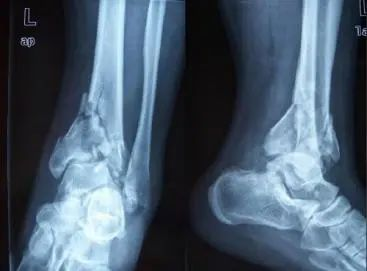

高能量损伤引起的Pilon骨折是临床常见的骨折之一。此类骨折波及负重关节面与干骺端的胫骨远端骨折,占下肢骨折的1%,占胫骨骨折的3%~10%。由于骨碎块多,常伴有严重的软组织坏死和肿胀,手术操作难度相对较大,容易并发症坏死和感染、骨折不愈合及创伤性关节炎。

因胫骨Pilon骨折常由高处坠落及车祸等高能量损伤所致,所以其关节面常为粉碎性骨折,移位明显,干骺端有不同程度的压缩,同时多伴有腓骨骨折、严重软组织损伤,骨折远端为松质骨,难以坚强固定。Pilon骨折的治疗方法较多,包括非手术方法、切开复位内固定、外固定支架固定及各种方法联合应用。